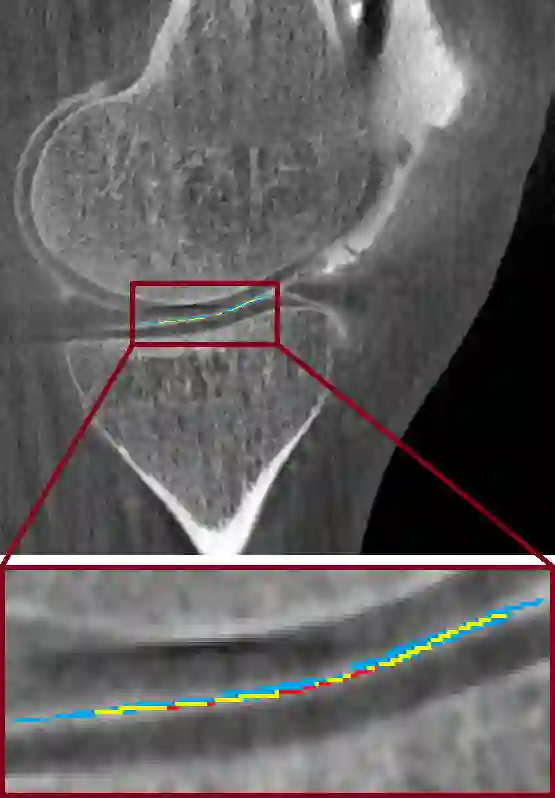

Analyzing knee cartilage thickness and strain under load can help to further the understanding of the effects of diseases like Osteoarthritis. A precise segmentation of the cartilage is a necessary prerequisite for this analysis. This segmentation task has mainly been addressed in Magnetic Resonance Imaging, and was rarely investigated on contrast-enhanced Computed Tomography, where contrast agent visualizes the border between femoral and tibial cartilage. To overcome the main drawback of manual segmentation, namely its high time investment, we propose to use a 3D Convolutional Neural Network for this task. The presented architecture consists of a V-Net with SeLu activation, and a Tversky loss function. Due to the high imbalance between very few cartilage pixels and many background pixels, a high false positive rate is to be expected. To reduce this rate, the two largest segmented point clouds are extracted using a connected component analysis, since they most likely represent the medial and lateral tibial cartilage surfaces. The resulting segmentations are compared to manual segmentations, and achieve on average a recall of 0.69, which confirms the feasibility of this approach.